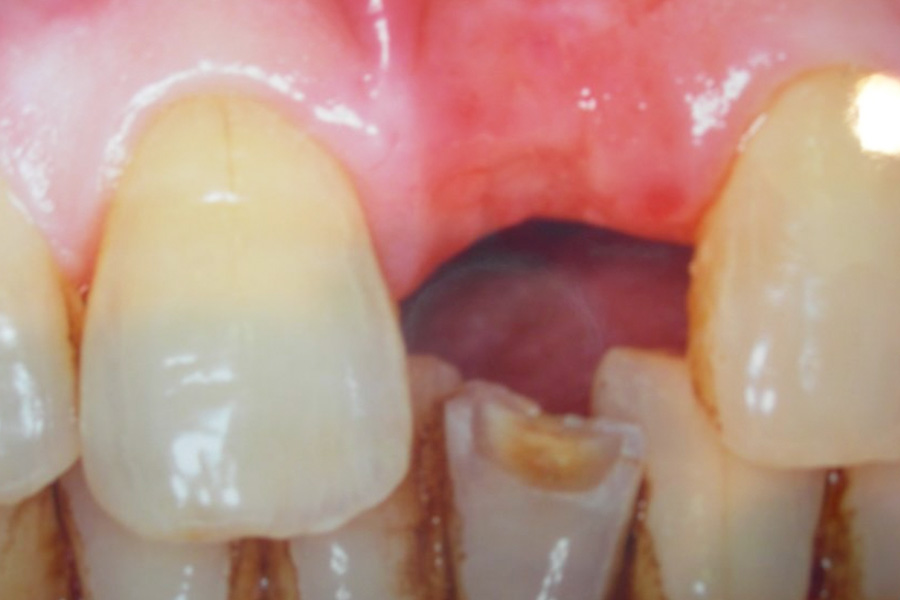

- 天然歯に馴染む前歯にしたい

- 上顎前歯インプラント治療(e-max)

- 歯髄壊死、歯根吸収、歯肉退縮、ブラックトライアングル